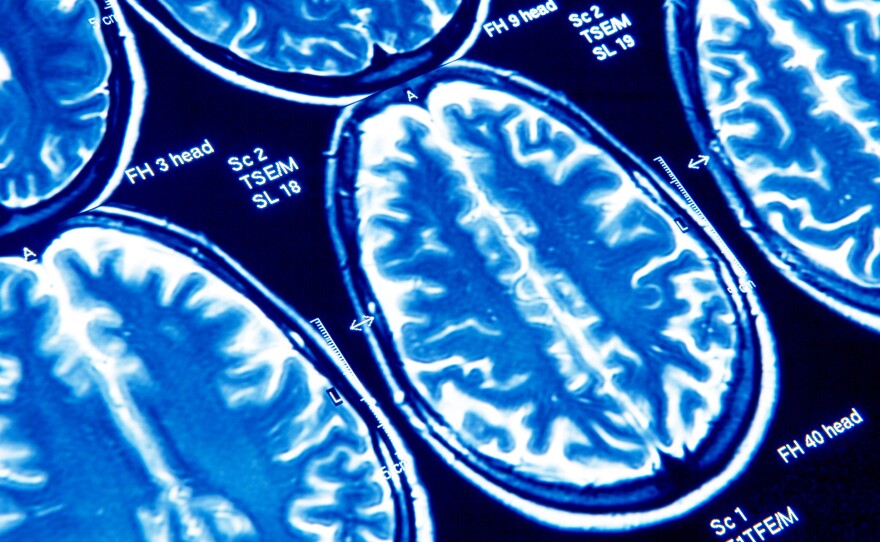

Most people who say they've had a concussion say they sought out medical care at the time.

Science Photo Libra/Getty Images